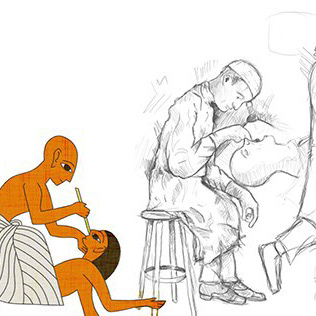

Illustration to show the vascularitation of the shoulder and diferent anatomical variants. It was made for a presentation of endovascular treatment of shoulder capsulitis.

First I draw the sketck on the iPad Pro, with the Sketchbook Software. After that, I move to Photoshop CC where, with a digital watercolour brush I painted and give the details.

I draw the anatomical variants over the same first draw but decided to desaturate the main artery so the variant could stand out.

I draw the anatomical variants over the same first draw but decided to desaturate the main artery so the variant could stand out.